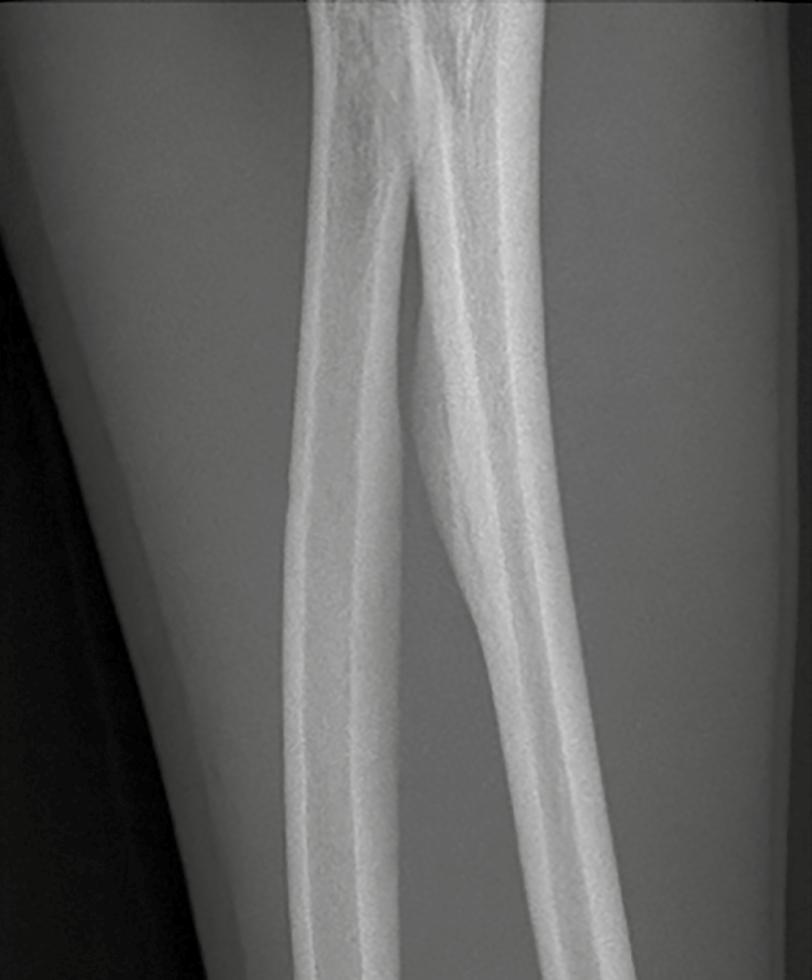

óseas, pero por sí sola no siempre permite distinguir entre lesiones benignas y malignas. Aunque la destrucción completa de la cortical suele asociarse con tumores malignos de alto grado, también puede observarse en entidades benignas agresivas como el EG o la osteomielitis (Figura 7 ). Por otro lado, una destrucción más uniforme y menos invasiva puede presentarse tanto en lesiones benignas como en tumores de bajo grado. En casos como la displasia fibrosa o el condrosarcoma de bajo grado, es típico observar un aspecto festoneado de la cortical.

En tumores malignos de células pequeñas y redondas, como el sarcoma de Ewing, el linfoma óseo o el osteosarcoma de células pequeñas, el aspecto de la cortical puede engañar. En la radiografía, la cortical puede parecer casi intacta, pero en realidad estos tumores infiltran el hueso a través de los canales de Havers, mostrando un patrón permeativo (Figura 9). A menudo, se acompañan de masas de tejido blando significativas; mientras que los signos de destrucción ósea pueden ser mínimos o incluso imperceptibles en una evaluación inicial, lo que hace necesario un análisis más detallado y contextual.

Figura 7. Destrucción cortical. 1. Osteosarcoma con destrucción cortical irregular (flecha amarilla). 2. Sarcoma de Ewing con destrucción cortical (flecha roja) y reacción perióstica agresiva (rombos azules). Adaptada de: Jan van der Woude R, Smithuis R. Bone tumors. Differential diagnosis [Internet]. 2010 [consultado 2025 oct 13]. Disponible en: https:// radiologyassistant.nl/musculoskeletal/bone-tumors/differential-diagnosis 1 2

Figura 8. El abombamiento. 1. Fibroma condromixoide: una lesión benigna, bien definida y expansiva con destrucción regular del hueso cortical y una capa periférica de hueso nuevo (flecha roja). 2. Tumor de células gigantes: Una lesión localmente agresiva con destrucción cortical, expansión y una capa periférica delgada e interrumpida de hueso nuevo; observar la amplia zona de transición hacia la cavidad medular, lo cual indica un comportamiento agresivo (flecha amarilla). Adaptada de: Jan van der Woude R, Smithuis R. Bone tumors. Differential diagnosis [Internet]. 2010 [consultado 2025 oct 13]. Disponible en: https://radiologyassistant.nl/ musculoskeletal/bone-tumors/differential-diagnosis

Figura 9. Destrucción cortical. Sarcoma de Ewing con crecimiento permeativo a través de los canales de Havers acompañado de una gran masa de tejido blando. 1. La radiografía no muestra signos de destrucción cortical. Tomada de: Jan van der Woude R, Smithuis R. Bone tumors. Differential diagnosis [Internet]. 2010 [consultado 2025 oct 13]. Disponible en: https:// radiologyassistant.nl/musculoskeletal/bone-tumors/differential-diagnosis